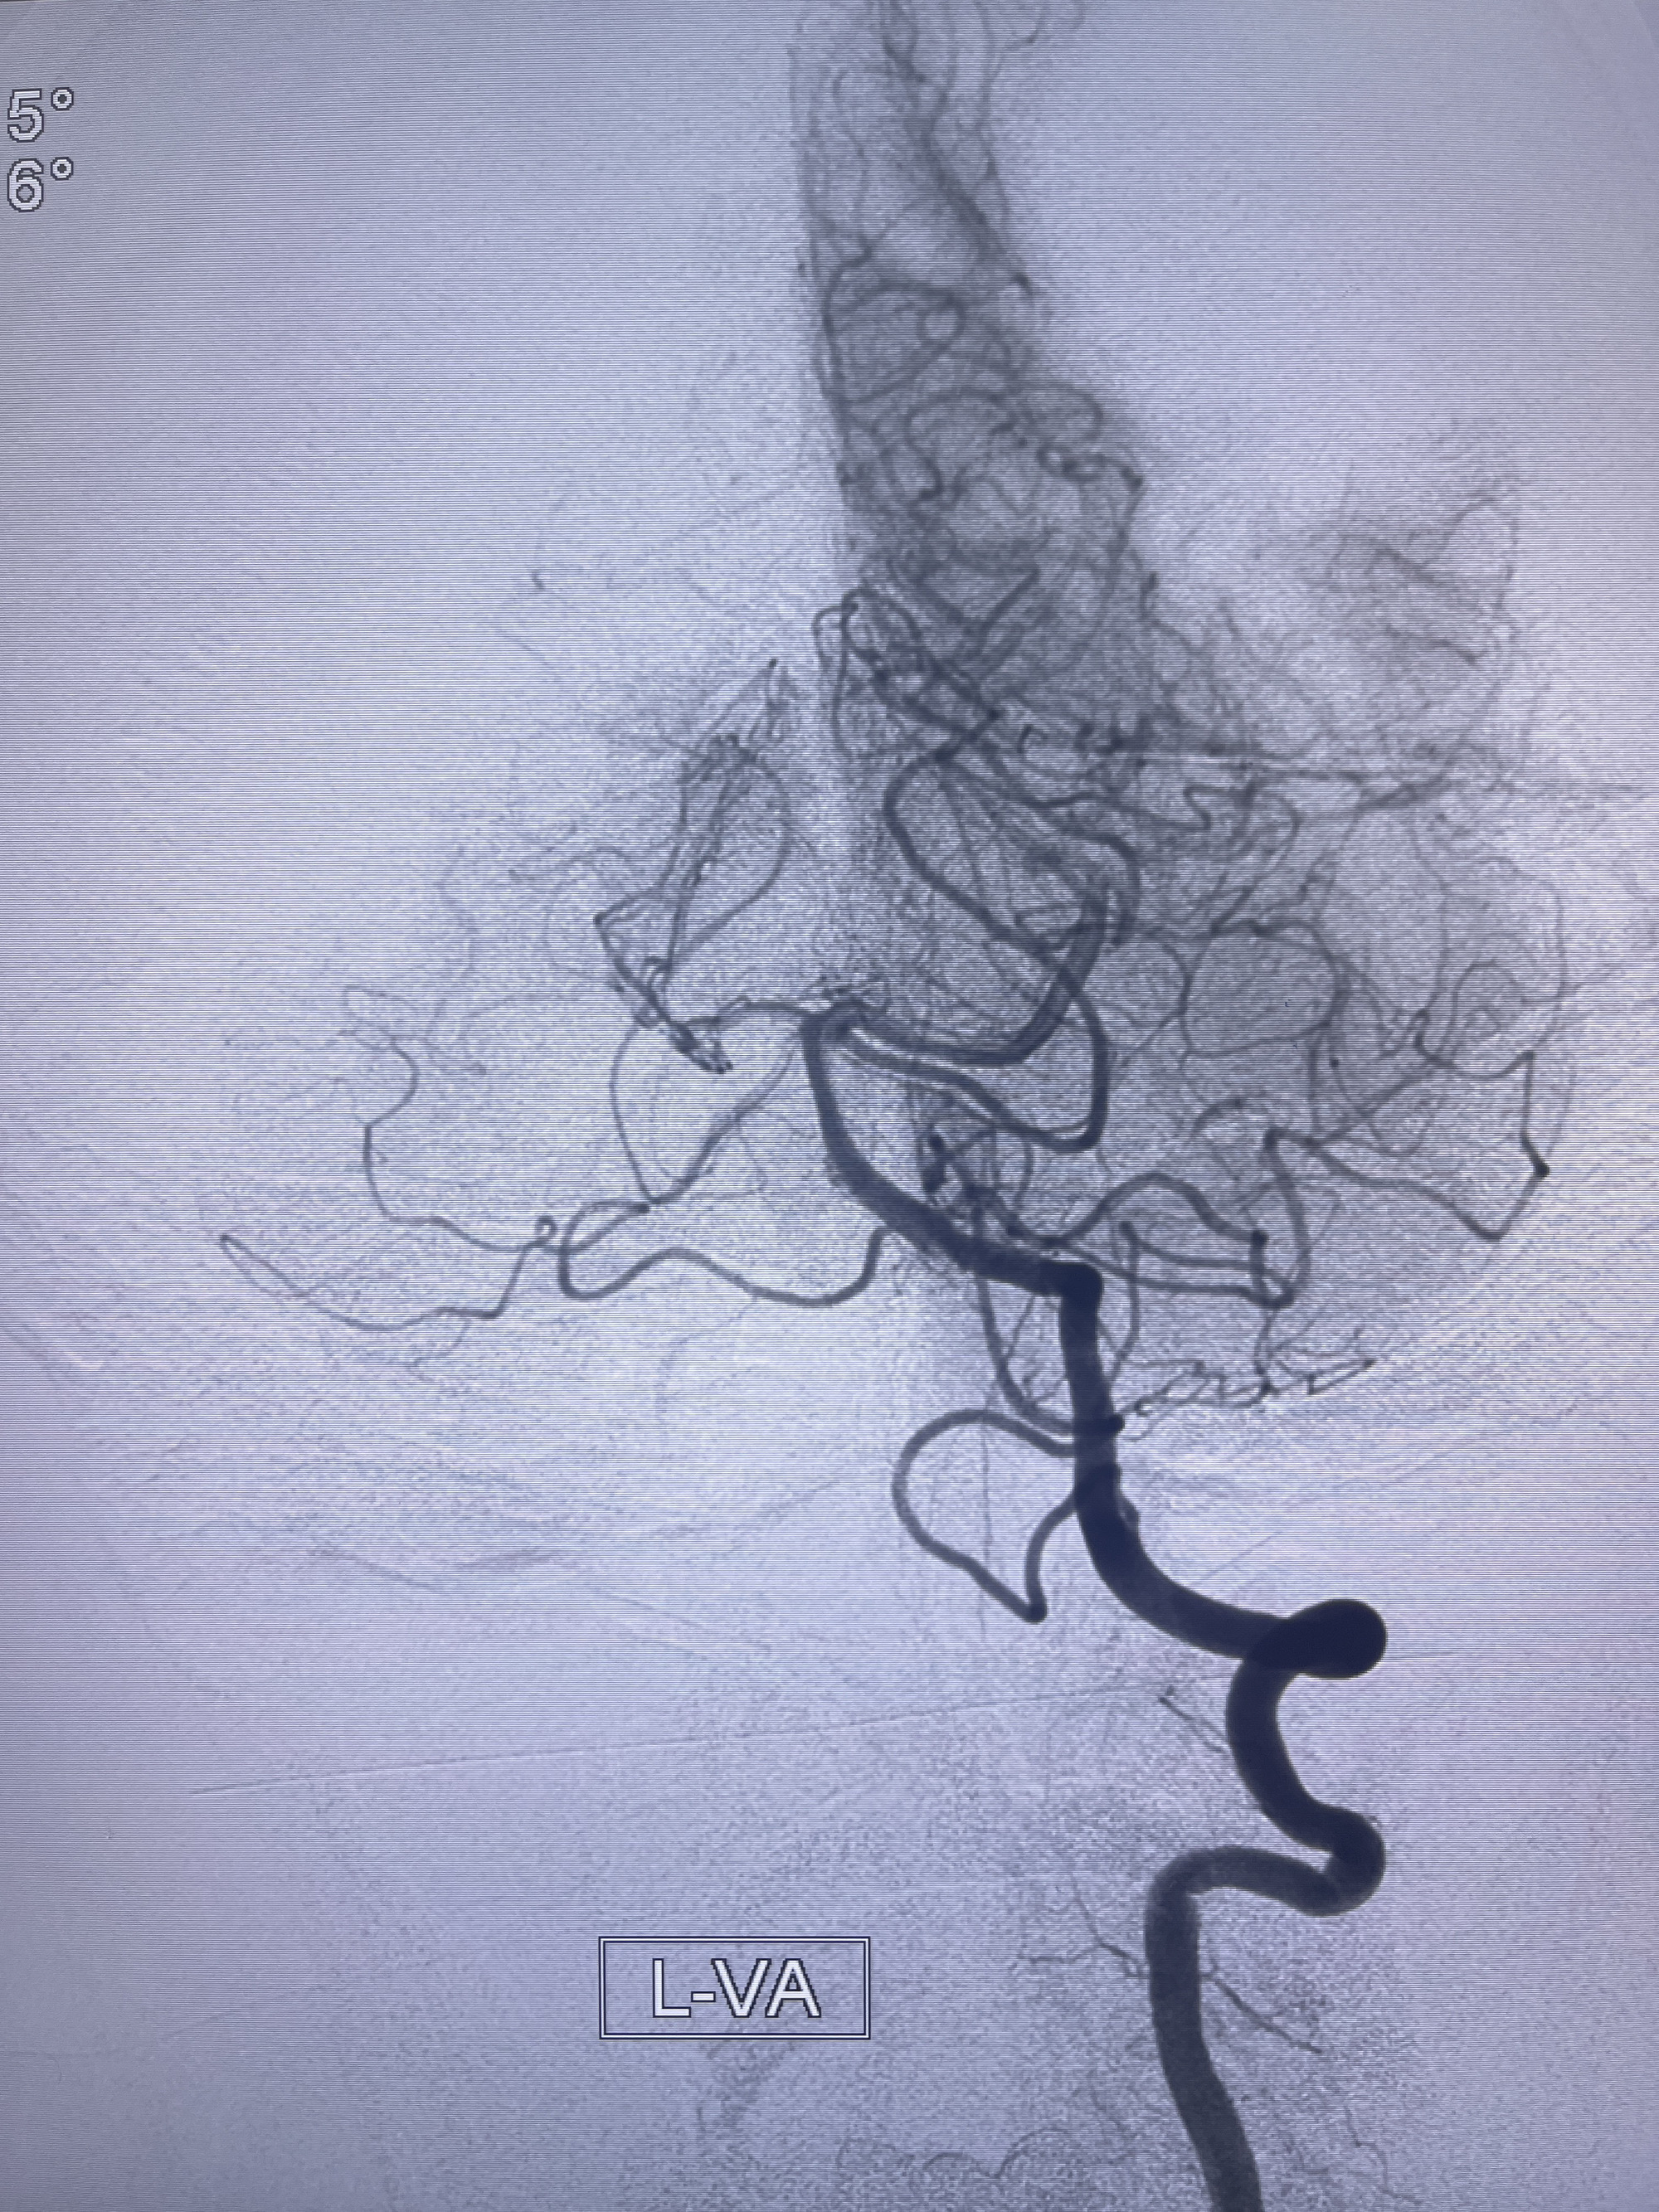

202.04.28脑血管造影:右侧大脑后动脉远段闭塞,右侧椎动脉V4段可见“囊状造影剂填充影”,大小7.64*7.65mm,可见PICA由动脉瘤发出;

1.普通支架辅助弹簧圈栓塞?

2.密网支架辅助弹簧圈栓塞?